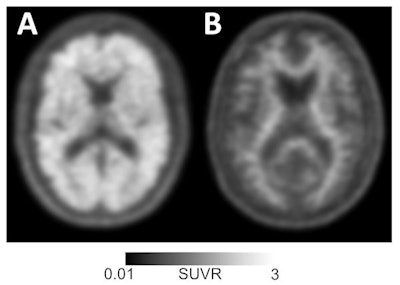

The accumulation of amyloid protein plaques and tau protein tangles in the brain is the hallmark of Alzheimer's disease. Until recently, amyloid plaques could be detected only after death through an autopsy of brain tissue.

This phase of the IDEAS trial included 11,409 patients. Before amyloid PET scans, Alzheimer's disease was the leading suspected cause of cognitive impairment in 8,785 (77%) subjects. Baseline PET scans then revealed 6,905 subjects (median age, 75 years) with mild cognitive impairment and 4,504 participants (median age, 77 years) with dementia.

Among the subjects with PET scans positive for amyloid accumulation, 3,817 people (55%) were confirmed to have mild cognitive impairment and 3,154 (70%) had dementia. Nine PET scans could not be interpreted.

As a result, 2,860 patients (25%) had their diagnosis changed from Alzheimer's disease to non-Alzheimer's, while 1,201 (11%) patients went from not having the disease to a confirmed case of the condition. When there were positive amyloid PET results, Alzheimer's diagnoses increased from 80% before imaging to 95% after the scans. For patients with a negative scan, the rate of Alzheimer's diagnoses decreased from 71% before PET to 10% after imaging.